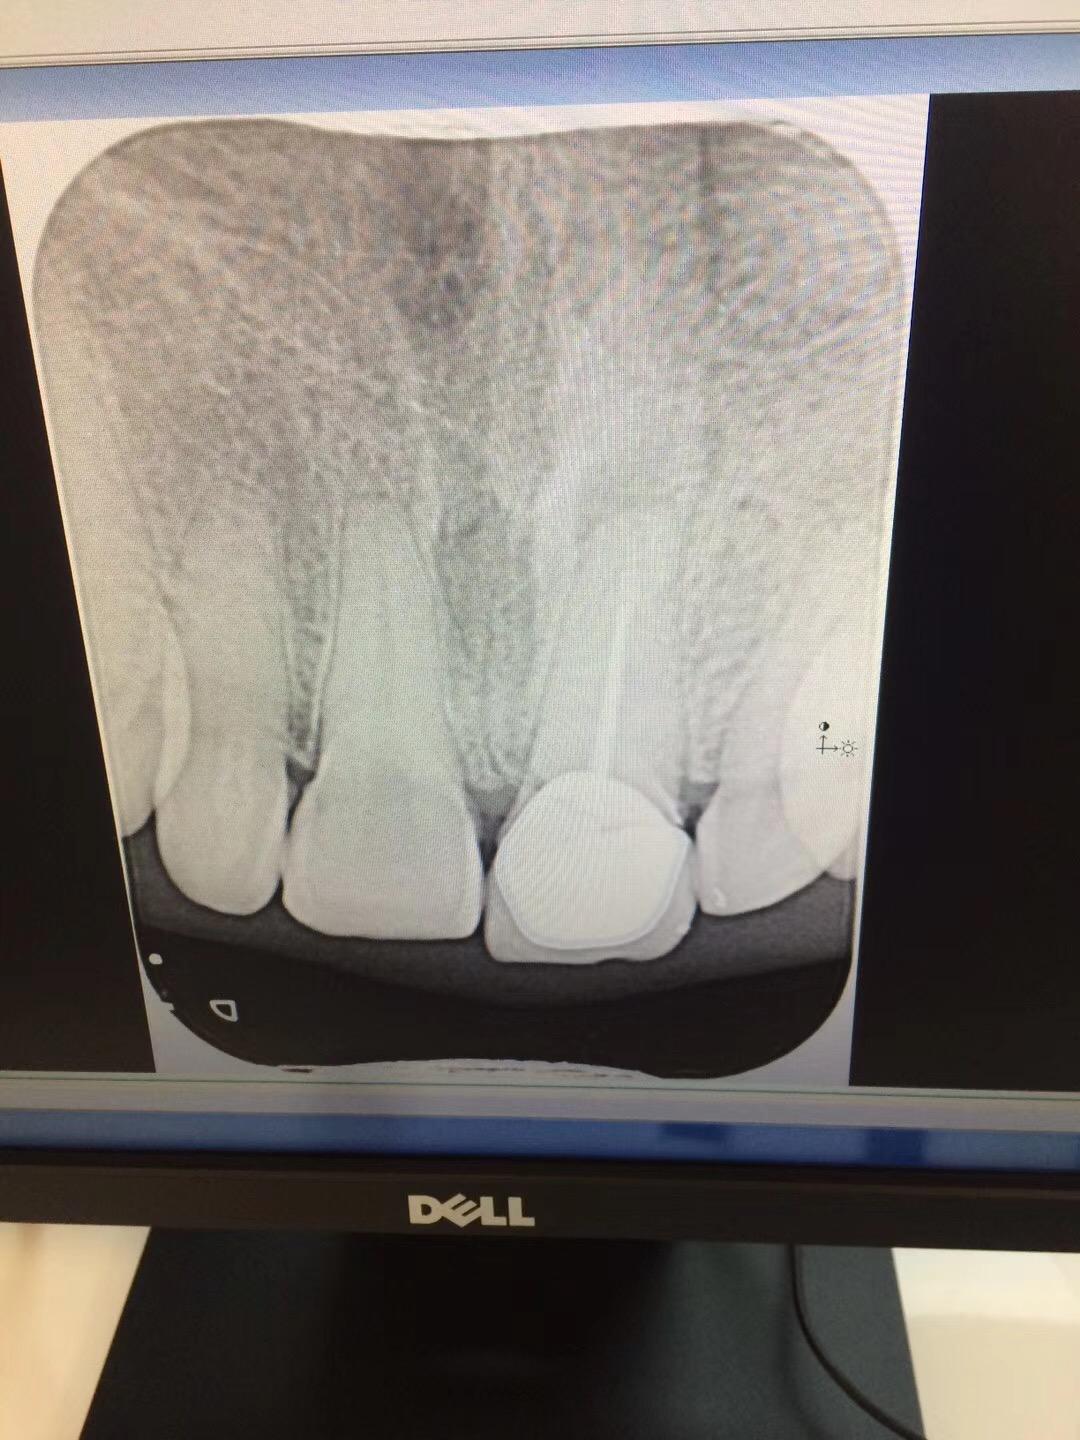

圈出来的小牙齿就是畸形中央尖所导致的牙髓坏死及根尖周炎症

牙齿无症状的根尖周炎(图4 和5)是由牙髓坏死引起的,并且通常是在